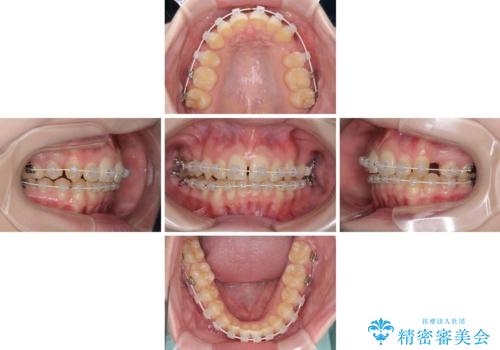

八重歯を短期間で改善 ワイヤー装置による抜歯矯正

- 著しい八重歯を気にして来院された患者様です。

片側の八重歯であり上顎の正中がずれていたため、上顎左右第一小臼歯2本を抜歯して排列することとしました。